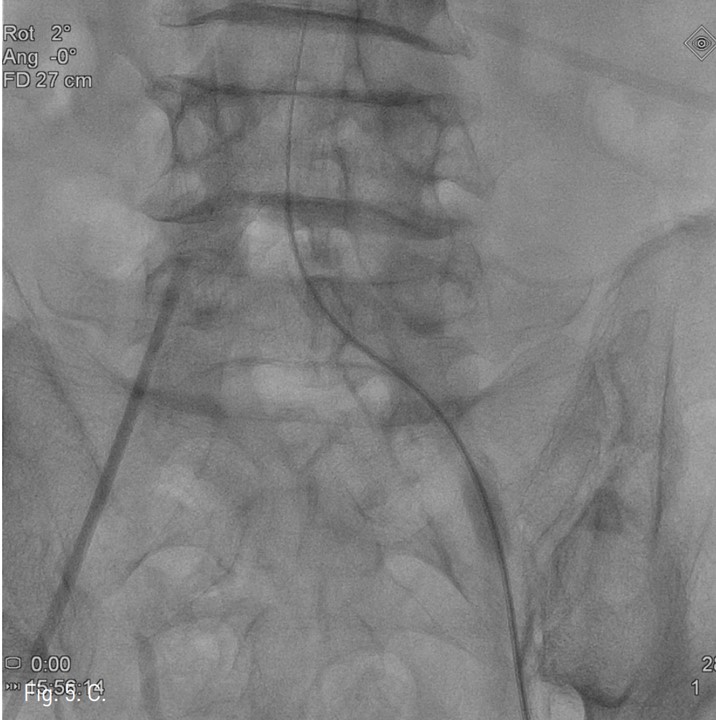

컴퓨터단층촬영 혈관조 영술과 고식적 혈관조영술에서 우측 총장골동맥에 석회화를 동반한 80%정도의 심한 협착이 있고, 좌측 총장골동맥에서 외장골동맥에 석회화를 동반한 완전 폐쇄의 소견이 있다 (Fig. 1A, IB). 우총대퇴동맥의 근위부에 10mm x 29mm Zenesis stent를 설치하였다 (Fig. 2). 0.035 inch guidewire로 좌측 총장골동맥의 기시부 폐쇄부위 통과를 시도하였으나 가성내강에서 진성내강으로 재진입이 되지 않았다 (Fig. 3). 좌측 외장골동맥 진성내강 내에 있는 ‘L-자’ 표시방향의 outback device가 보인다 (Fig. 4A), 좌측 외장골동맥 진성내강 내에 있는 'T-자’ 표시방향의 outback device가 보인다(Fig. 4B). Outback device를 이용하여 동맥내막을 천자후 0.014 inch guidewire를 가성내강 내로 진입시켰지만 좌측 총장골동맥-외장골동맥경 계부위에서 더 이상 진행되지 않았다 (Fig. 4C). 0.014 inch guidewire를 따라서 Davis catheter를 가성내강 내로 진입시키고 (Fig. 5A), 10mm snare를 삽입하여 Simmon catheter내부에 있던 microwire를 전진시켜 snare로 잡아 좌측 sheath로 뽑아내어 (Fig. 5B), 5Fr. Davis catheter를 대동맥 내부로 진입시켰다(Fig. 5C). 양측 총장골동맥 및 좌측 외장골동맥 스텐트 설치후 대동맥장골동맥조영술상에서 양측 장골동맥의 완전한 재개통을 보인다 (Fig. 6).

Fig. 3.

Fig. 3. Antegrade subintimal passage of 0.035 inch guidewire into the distal true lumen was failed.